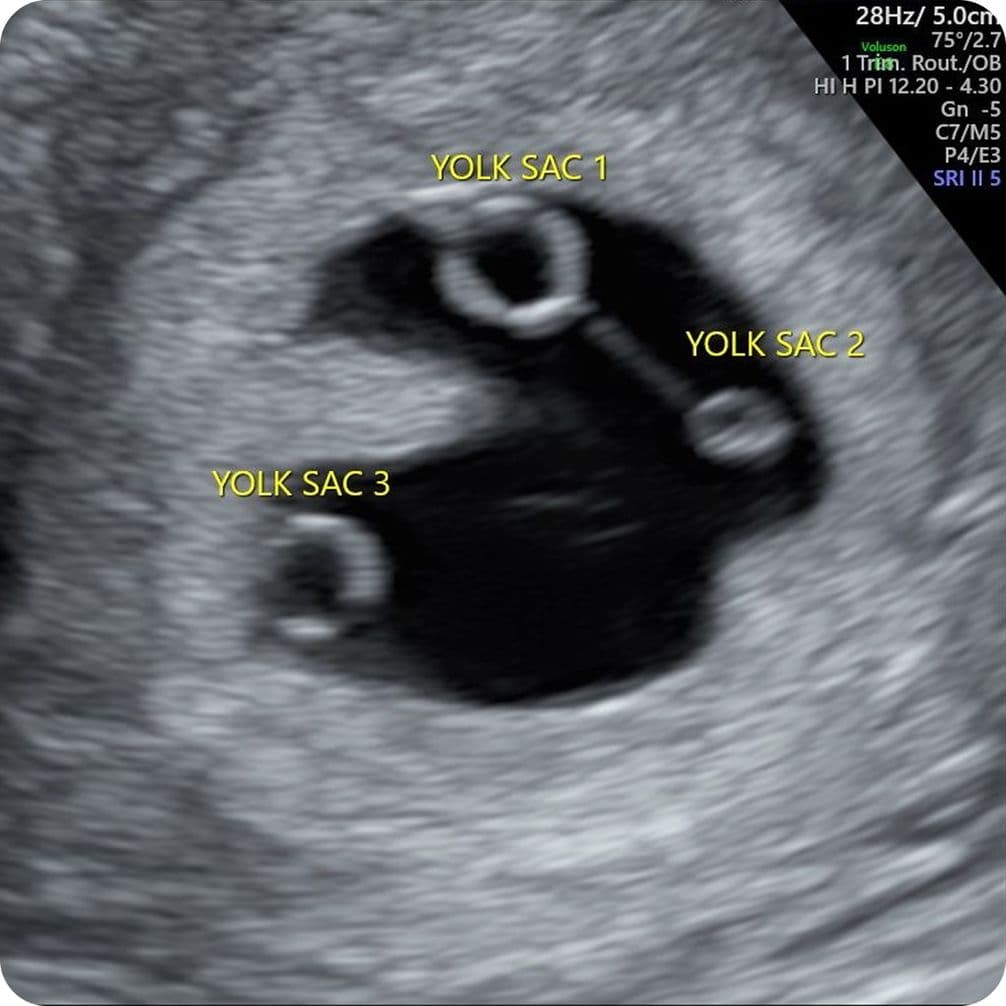

Our sonographer started the scan. The grainy black and white picture on the screen was unreadable to someone experiencing pregnancy for the first time. She was quiet and taking her time – could she see anything? She announced that there was a “yolk sac” (that’s what they call a baby before it becomes a foetus) – but it didn’t stop there. “Oh there’s another one, and… another one.” What? There’s three? Triplets – me? The woman who thought she didn’t even want children for most of her life.

The three of us in the room were in shock. I looked at my partner and just burst into laughter. Surely this was a joke? As a father already to two children from a previous relationship, he genuinely looked horrified. This wasn’t in the plan. She told us that one of the yolk sacs was small compared to the other two, and that it was likely to vanish by the next scan; something we later learned was common, called Vanishing Twin Syndrome. “Well, this explains why you feel so poorly,” the sonographer said.